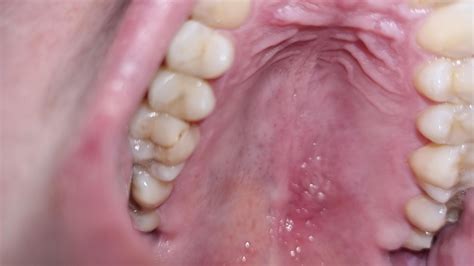

Get a sunburn on palate of mouth can be unbelievably thwarting and sore, turning simple daily activities like feeding, imbibing, or still verbalise into a rootage of discomfort. The roof of the mouth, known medically as the palate, is a sensible area lined with delicate mucosal tissue. Because it is invariably in contact with everything we ingest, it is highly susceptible to thermal wound, chemical irritation, and various medical conditions. Whether you have accidentally scorched your mouth with a piping hot slice of pizza or are dealing with a mysterious burning superstar that won't go away, read the root drive is the maiden step toward finding relief.

The palate is vulnerable to a variety of internal and external ingredient. Identifying the perpetrator is essential, as the intervention for a thermal burn will differ importantly from handling for an allergic reaction or an fundamental infection.

Distinguishing Between Types of Palate Irritation

Understanding the rigour and nature of your discomfort helps in choosing the right path to recovery. Below is a comparative overview of mutual topic regard the palate: